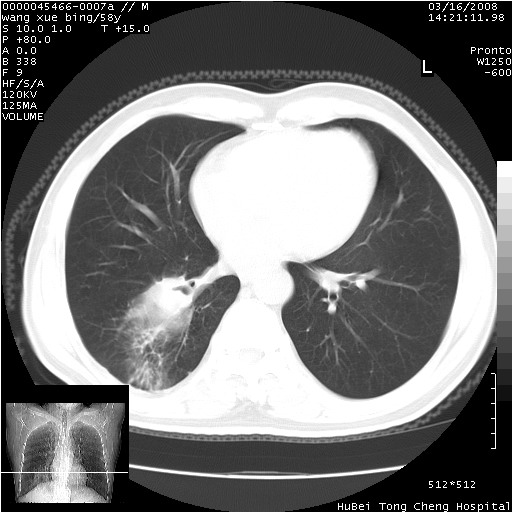

胸部ct轴位平扫(层厚10mm,螺距1.5,重建间隔10mm),图像如下:

右肺下叶周围型肺癌伴空洞形成!征象比较明显!分叶、毛刺、胸膜凹陷征、厚壁空洞,壁结节!

空洞内壁不规整,有壁结节,周围有毛刺,支持癌性空洞。

空洞壁厚,不规则,其内可见壁结节,周围可见毛刺及阻塞性炎变,多考虑癌性病变.